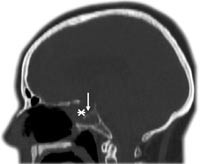

Pasient 2. En 58 år gammel kvinne ble operert for tredje gang med transseptal, transsfenoidal tilgang for residiv av kromofobt hypofyseadenom. Pasienten hadde økende synsfeltsutfall, og adenomet vokste infiltrerende i skallebasis med gjennomvekst til sinus sphenoidalis. Etter inngrepet oppstod rhinoré, og CT caput viste pneumatocephalus. To endoskopiske operasjoner med transnasal tilgang ble gjennomført for å lukke lekkasjen, men begge var mislykte. CT-bilde viste en stor beindefekt i den fremre veggen og i gulvet av sella turcica (fig 2). Nesesekretet inneholdt 8,2 mg/l betasporprotein. Tredje forsøk på å lukke lekkasjen ble gjennomført med natriumfluoresceinfarging (fig 3). Defektene ble dekket med autolog fascia lata. På grunn av hydrocephalus ble det lagt en ventrikuloperitoneal shunt. Den postoperative CT-undersøkelsen viste ikke intrakranial luft, og ved kontroll etter fem måneder hadde hun ikke tegn til likvoré.